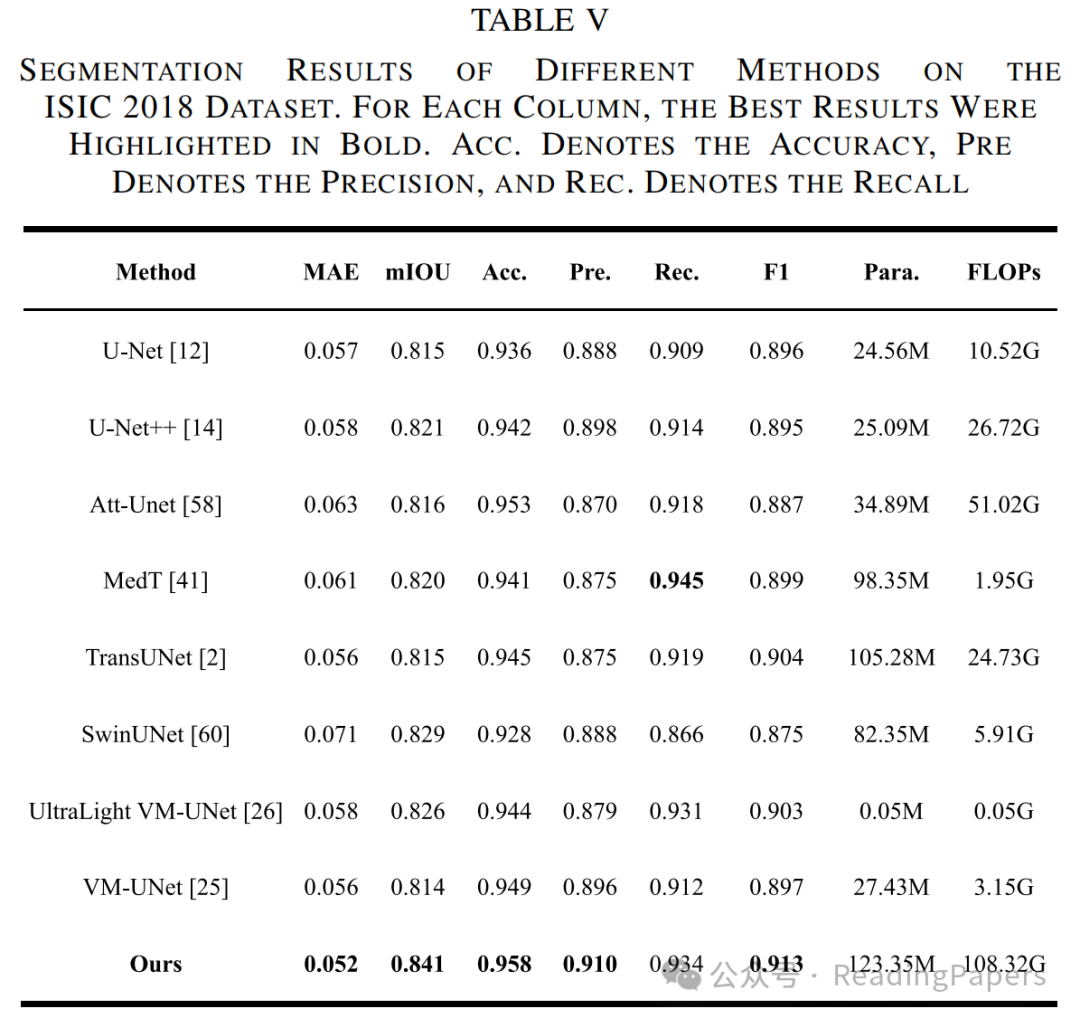

Transformer通过自注意力机制在医学图像处理中取得了显著进展,能够建模长距离语义依赖关系,但其缺乏卷积神经网络(CNN)捕捉局部空间细节的能力。本文提出了一种基于混合CNN-Transformer(MixFormer)特征提取骨干网络的新型分割网络,旨在提升医学图像分割的效果。MixFormer网络在下采样过程中无缝集成了Transformer和CNN架构的全局和局部信息。为了全面捕捉跨尺度的视角,作者引入了多尺度空间感知融合(MSAF)模块,有效实现了粗粒度与细粒度特征表示之间的交互。此外,作者还提出了混合多分支扩张注意力(MMDA)模块,用于在编码和解码阶段之间弥合语义差距,同时强调特定区域。最后,作者采用基于CNN的上采样方法来恢复低级特征,显著提高了分割精度。通过在多个主流医学图像数据集上的实验验证,MixFormer表现出卓越的性能。在Synapse数据集上,该方法达到了82.64%的平均Dice相似系数(DSC)和12.67 mm的平均Hausdorff距离(HD)。在自动心脏诊断挑战(ACDC)数据集上,DSC达到了91.01%。在国际皮肤成像协作(ISIC)2018数据集上,模型的平均交并比(mIoU)为0.841,准确率为0.958,精确率为0.910,召回率为0.934,F1得分为0.913。在Kvasir-SEG数据集上,平均Dice为0.9247,mIoU为0.8615,精确率为0.9181,召回率为0.9463。在CVC-ClinicDB数据集上,平均Dice为0.9441,mIoU为0.8922,精确率为0.9437,召回率为0.9458。这些结果表明,MixFormer在分割性能上优于大多数主流分割网络,如CNN和其他基于Transformer的结构。